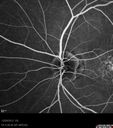

59-year-old man has macular dystrophy in both eyes. He saw Dr. Gass in 1989, at which time Dr. Gass thought it might be post inflammatory. Interestingly, at this point he still does not have a diagnosis other than macular dystrophy. His vision since he was here last is reasonably stable.

He has been diabetic for eight years. He had LASIK surgery done in 1998. He was a high myope, about a -10 and now he is about a -3. He had some vision changes in medical school in the 1980s and saw Dr. Gass for that. He had some pigment epithelial irregularities in both eyes. Dr. Gass felt maybe this was an atypical case of previous AMPPE. Otherwise he is in good health. He had strabismus as a child and had muscle surgery. He is color blind, along with many people in his family, and as far as he knows, it is congenital.

VISUAL ACUITY: Vision OD is 20/25, OS is 20/30. IOP: OD 14, OS 13. The lenses are clear.

OD: Vertical C/D ratio is 0.2. There are no vitreous cells. The retinal vessels are slightly attenuated. The retina is very thin looking.

OS: Vertical C/D ratio is 0.2. Again, the retinal vessels are attenuated. The retina does appear to be thin looking.

OCT SCAN: The OCT scan shows retinal atrophy in both eyes.

1. RETINAL ATROPHY – BOTH EYES